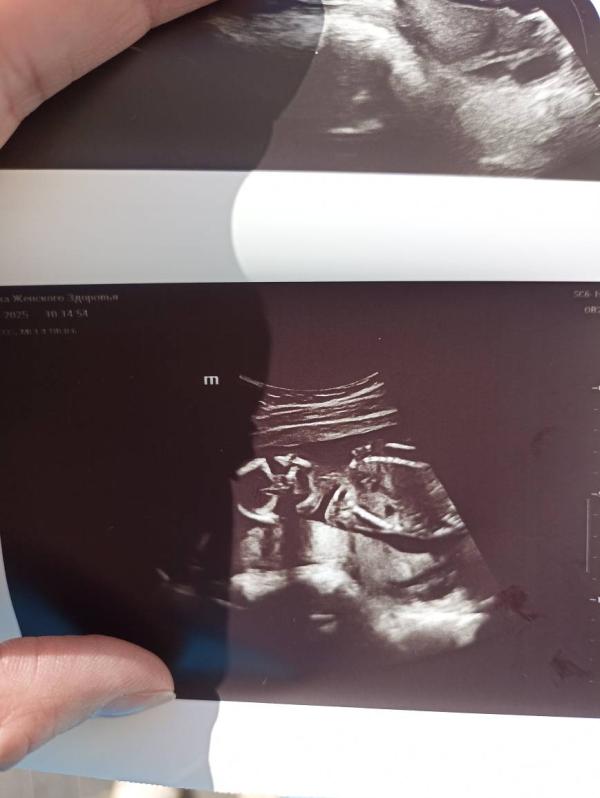

post image

Посмотрели сегодня шейку, все хорошо. Заодно посмотрели пол, подтвердили мальчишку 🥰 Крутился, вертелся, как егоза, еле рассмотрели 😅

Для себя: 16,5 недели